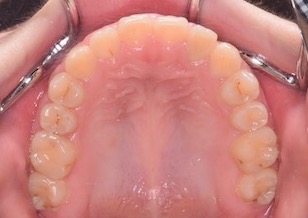

上顎骨の劣成長に起因する骨格性反対咬合(上下顎骨の前後的な位置不正が原因)で、前歯部は反対咬合となっており咀嚼障害を認めます。 上下顎歯列において叢生(ガタガタの歯並び)と 上下顎歯列の正中線のズレが認められます。 左側上下顎第一大臼歯は交叉咬合となっています。レントゲン所見では、上顎左側犬歯が方向異常にてその隣の側切歯の歯根にぶつかって埋伏していました。

Before Ⅳの写真は、治療中のパノラマレントゲンです。(上顎左側犬歯が方向異常にてその隣の側切歯の歯根にぶつかって埋伏しています。)